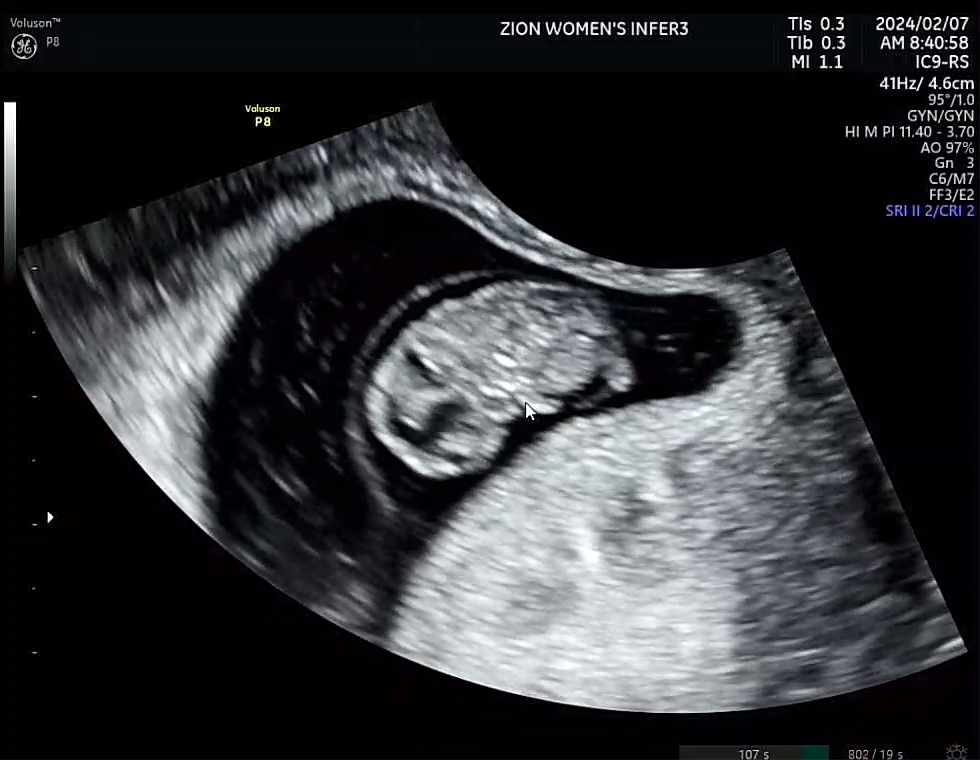

젤리곰 옆태만 보고왔어요 ㅠㅠㅋㅋㅋ

8주 5일입니다 7주에 병원갔을 땐 8mm였는데 그새 2cm가 되었더라구요! 완벽한 젤리곰을 기대하고 갔는데... 앞(?)을 안보여주고 옆태만 보여서 약간 실망했지만..ㅋㅋㅋ 아침에 시리얼을 먹고가서그런지 애기가 파닥파닥 움직여줘서 너무 웃기고 신기했네요 너무 격정적이어서 의사쌤도 웃으시면서 "자기 잘 있다고 움직여주네요~" 이러시더라구요ㅎㅎㅎ 다음주에 피검사 결과들으러가면서 촘파 볼건데 좀 더 사람같은 젤리곰 볼 수 있겠죠!?